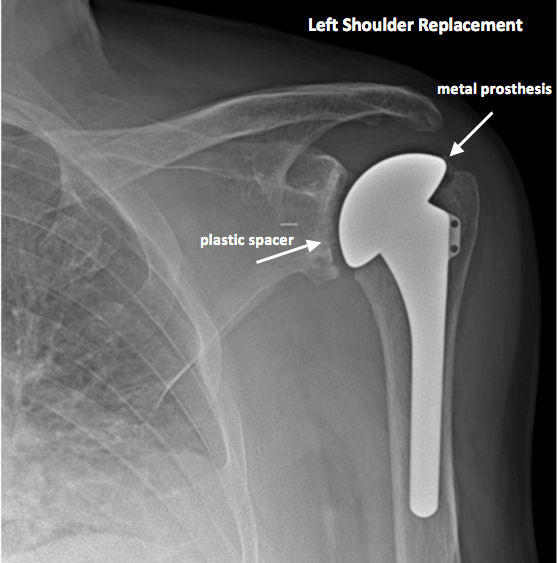

Shoulder Replacement X-Ray . Shoulder replacement removes damaged areas of bone and replaces them with parts made of metal and plastic (implants). If there is an irreparable rotator cuff. Shoulder arthroplasties are a common procedure, being third in joint replacements after knees and hips, and are used to treat a number of. This allows the patient to use the deltoid muscle instead of the torn rotator cuff to lift the arm. Patient suitability for an anatomic shoulder arthroplasty. A standard total shoulder arthroplasty, also known as anatomic total shoulder arthroplasty or total shoulder replacement, aims to replace both the.

Patient suitability for an anatomic shoulder arthroplasty. Shoulder replacement removes damaged areas of bone and replaces them with parts made of metal and plastic (implants). This allows the patient to use the deltoid muscle instead of the torn rotator cuff to lift the arm. Shoulder arthroplasties are a common procedure, being third in joint replacements after knees and hips, and are used to treat a number of. A standard total shoulder arthroplasty, also known as anatomic total shoulder arthroplasty or total shoulder replacement, aims to replace both the. If there is an irreparable rotator cuff.

Shoulder Replacement X-Ray Patient suitability for an anatomic shoulder arthroplasty. Patient suitability for an anatomic shoulder arthroplasty. This allows the patient to use the deltoid muscle instead of the torn rotator cuff to lift the arm. Shoulder replacement removes damaged areas of bone and replaces them with parts made of metal and plastic (implants). If there is an irreparable rotator cuff. Shoulder arthroplasties are a common procedure, being third in joint replacements after knees and hips, and are used to treat a number of. A standard total shoulder arthroplasty, also known as anatomic total shoulder arthroplasty or total shoulder replacement, aims to replace both the.